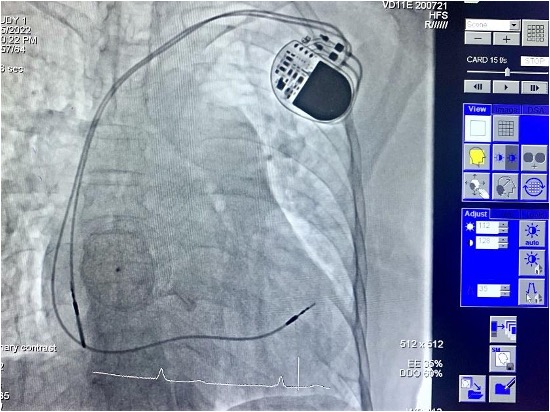

Qua hội chẩn, các bác sĩ quyết định chụp mạch vành cho người bệnh bằng kỹ thuật chụp mạch máu số hóa xóa nền DSA, đo kháng lực phổi, đóng thông liên nhĩ bằng dù qua da và đặt máy tạo nhịp vĩnh viễn, tiến tới ổn định nhịp tim và làm giảm tiến triển suy tim, giảm nguy cơ đột tử, cải thiện sức khỏe cho người bệnh.